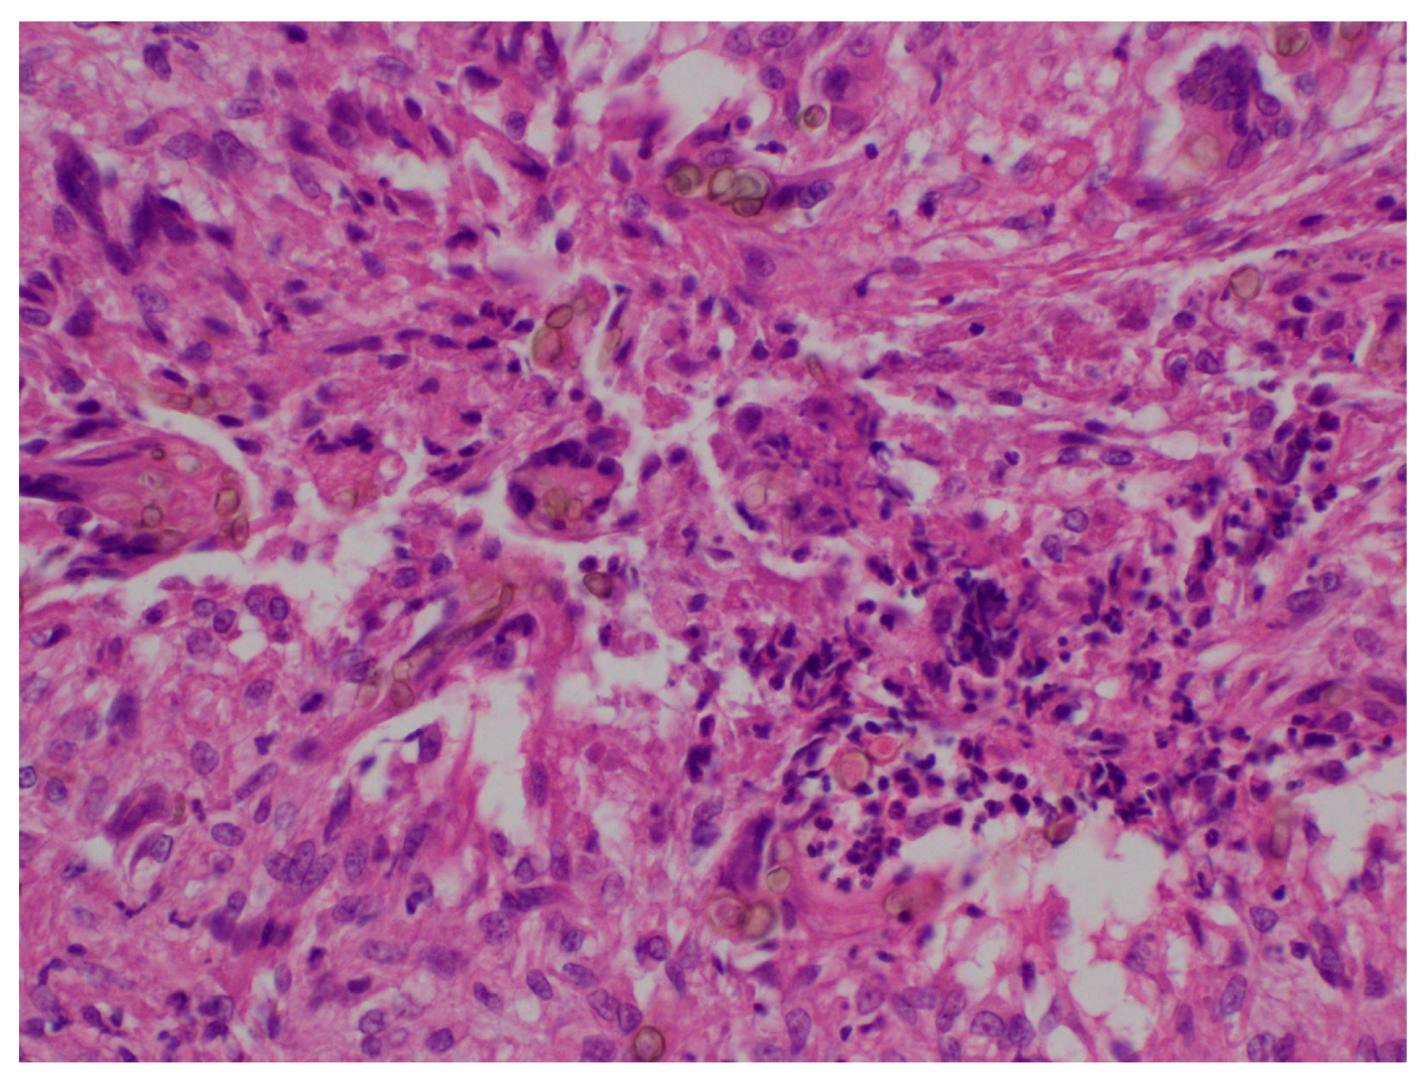

6. Histopathology

Granulomas with multinucleated giant cells, suppurative granulomas, and dermal fibrosis may be observed [8]. Hyphae and pigmented spores may also be observed, especially in the center of the lesion [18] (Figure 3).

In cases of rare black fungi, such as P. crystallina and C. cassiicola, pseudoepitheliomatous hyperplasia with hyperkeratosis and microabscesses in the epidermis can be observed. A mixed infiltrate with neutrophils, macrophages, lymphocytes, and plasma cells can be seen in the dermis. Also, pigmented septate hyphae and ovoid yeasts can be observed from the stratum corneum to the deep dermis, surrounded by necrotic tissue and multinucleated giant cells [14].

Figure 3. Tuberculoid granuloma and pigmented spores (HE 40×).